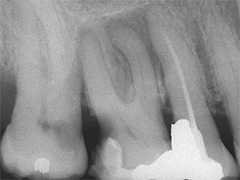

Der umfangreiche kariöse Defekt steuerte sehr bald hin auf die komplette Entfernung des Zahninnen­gewebes mit anschliessendem medikamentösen Wiederverschluss. Aufbissempfindlichkeit am Folgetermin ist immer Aufforderung zur erneuten Intensivsuche nach weiteren Kanälen, die hier einen 4. Ast zum Vorschein brachte. Nach 2 ausgelassenen Terminen

waren vorrangig Wiederherstellung von desinfizierender Einlage und provisorischer Füllung angezeigt. Eine weitere Woche später wurde in allen Kanälen das Medikament durch die endgültige Verschlussmasse ersetzt, worauf Zahn 36 mit 12-tägiger Verzögerung erneut zu rebellieren begann. Das hiess aus den hinteren Wurzeln Füllmaterial wieder raus und

Einlage erneut rein. Als es dann 4 Wochen später bei der hinteren Wur­zel aussen anzuschwellen begann und ein Medikamentenwechsel ohne Wir­kung blieb, wurden die hinteren Ka­näle abgefüllt und auch in gleicher Sitzung das überstopfte Material (Bild 1) mittels Resektion (Bild 2) von aussen entfernt.

Die ersten beiden Aufnahmen sind aus dem Jahr 1999, die 3. von 2006